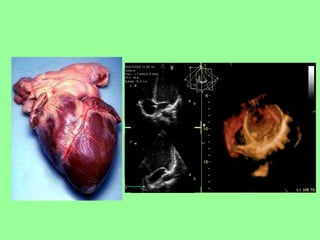

EL CORAZÓN

El corazón se localiza en el centro de la cavidad torácica, entre los pulmones.

EL CORAZÓN ES UN ÓRGANO MUSCULOSO HUECO DEL TAMAÑO DE UN PUÑO

EL CORAZÓN SE ENCUENTRA ENCERRADO EN UN SACO DE DOBLE PARED DENOMINADO PERICARDIO

EL CORAZÓN ESTÁ FORMADO POR UN TEJIDO MUSCULAR CONTRÁCTIL DENOMINADO MIOCARDIO. SUS CONTRACCIONES PROPULSAN LA SANGRE HACIA EL CUERPO A TRAVÉS DE LAS ARTERIAS.

ANATOMÍA DEL CORAZÓN Cayado aórtico Válvulas  semilunares El conjunto de pequeñas arterias y venas que llevan la sangre a los tejidos del propio corazón es el SISTEMA CORONARIO